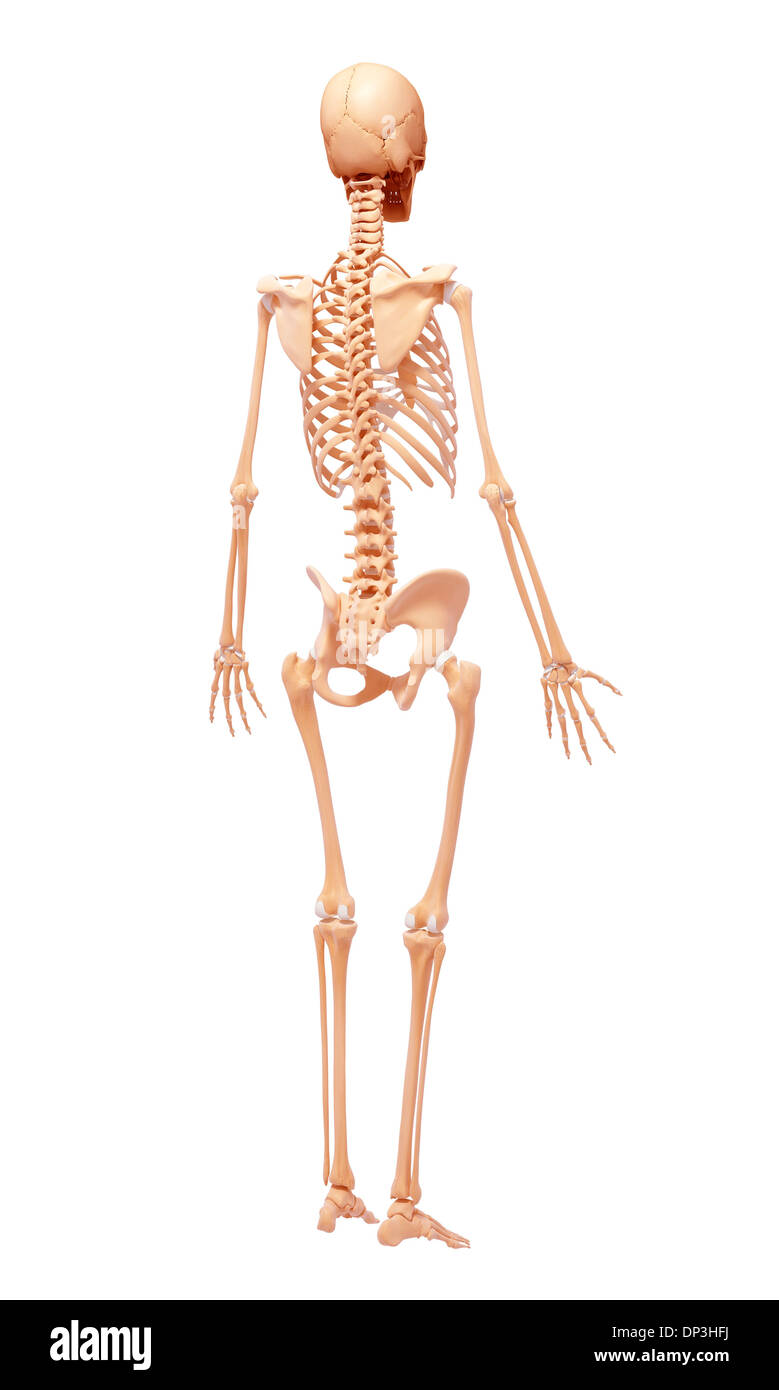

Human Skeleton, artwork Banque D'Imageshttps://www.alamyimages.fr/image-license-details/?v=1https://www.alamyimages.fr/human-skeleton-artwork-image65233158.html

Human Skeleton, artwork Banque D'Imageshttps://www.alamyimages.fr/image-license-details/?v=1https://www.alamyimages.fr/human-skeleton-artwork-image65233158.htmlRFDP3HFJ–Human Skeleton, artwork